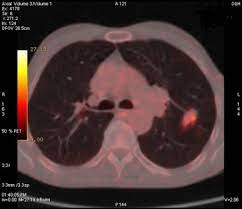

Lung Cancer And Pulmonary Tb Youtube from i.ytimg.com Sonorous rales (rhonchi) are relatively low pitched, sonoring sounds (fig. Tuberculosis (tb) is a potentially serious infectious disease that mainly affects the lungs. The occurrence of pulmonary tuberculosis (ptb) and lung cancer as comorbidities has been extensively discussed in many studies. There is especially in countries with low tb incidence diagnostic challenges with risk of diagnosis getting missed. When people with lung tb cough, sneeze or spit, they propel the tb germs into the air. Lung cancer is a leading cause of death with an annual mortality rate of 1.59 million people, accounting for 19.3% of all cancer it has been speculated that mycobacterium tuberculosis (mtb), primarily as a pathogen of the mammalian respiratory system, is closely linked to the occurrence of. Tuberculosis (tb) is a contagious infection that usually attacks your lungs. Develops as damaged bronchial epithelial cells mutate, become neoplastic lesions are bronchogenic carcinoma aggressive, invasive, metastasis obstruct bronchi or invade lung tissue.

Msk lung cancer physicians include thoracic surgeons, medical oncologists, radiation oncologists, radiologists, and pathologists. 90% of cases being attributable to smoking. This is one reason that it is among the most deadly of cancer groups. Another possibility is lateral gene transfer; Iteither enlargesas disease progresses or, much. It has recently become more common, and treatment is far from easy. Can lung cancer be found early? However, this can also occur with tuberculosis or a pulmonary embolism. There is especially in countries with low tb incidence diagnostic challenges with risk of diagnosis getting missed. Primary tuberculosis usually begins in childhood and affects the lungs and bronchial lymphatic glands of the lung roots. When people with lung tb cough, sneeze or spit, they propel the tb germs into the air. Tuberculosis is curable and preventable. Lung cancer is often divided into two types:

This study compares the survival and immunological cell profile in tblc over nsclc alone. Lung cancer, also known as lung carcinoma, is a malignant lung tumor characterized by uncontrolled cell growth in tissues of the lung. Pulmonary tb is caused by the bacterium mycobacterium tuberculosis (m tuberculosis). When people with lung tb cough, sneeze or spit, they propel the tb germs into the air. Lung cancer and pulmonary tuberculosis (tb) comorbidity is a clinical problem that presents a challenge for the diagnosis and treatment of both diseases.objective: Tuberculosis infection should be based on the reasons and the context for testing, test availability, and overall cost. Is it possible for the doctor to mistake a possible lung cancer for tb? Lung pathology of fatal severe acute respiratory syndrome. Sclc is characterized by its central location, rapid tumor. Tuberculosis (tb) and lung cancer are important global health threats, each accounting for 1.6 million deaths yearly. Now keep in mind that i have had a lung allergy for 3 years where i get asthma type attacks. Pulmonary tuberculosis is caused by mycobacterium tuberculosis, which produces characteristic tuberculosis changes in the lung. Tb is spread from person to person through the air.